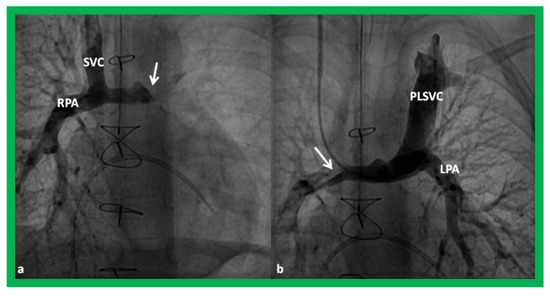

Figure 15.

Cineangiographic frames demonstrating a bilateral bidirectional Glenn procedure (Stage II). In (a), angiogram of the superior vena cava (SVC) illustrates opacification of the right pulmonary artery (RPA). The arrow in (a) shows the unopacified blood from a persistent left superior vena cava (PLSVC). In (b), an injection into the PLSVC illustrates opacification of the left pulmonary artery (LPA). The arrow in (b) shows the unopacified blood from the right SVC. Unobstructed flow from the respective SVCs into the pulmonary arteries is clearly seen. Reproduced from Reference [33].